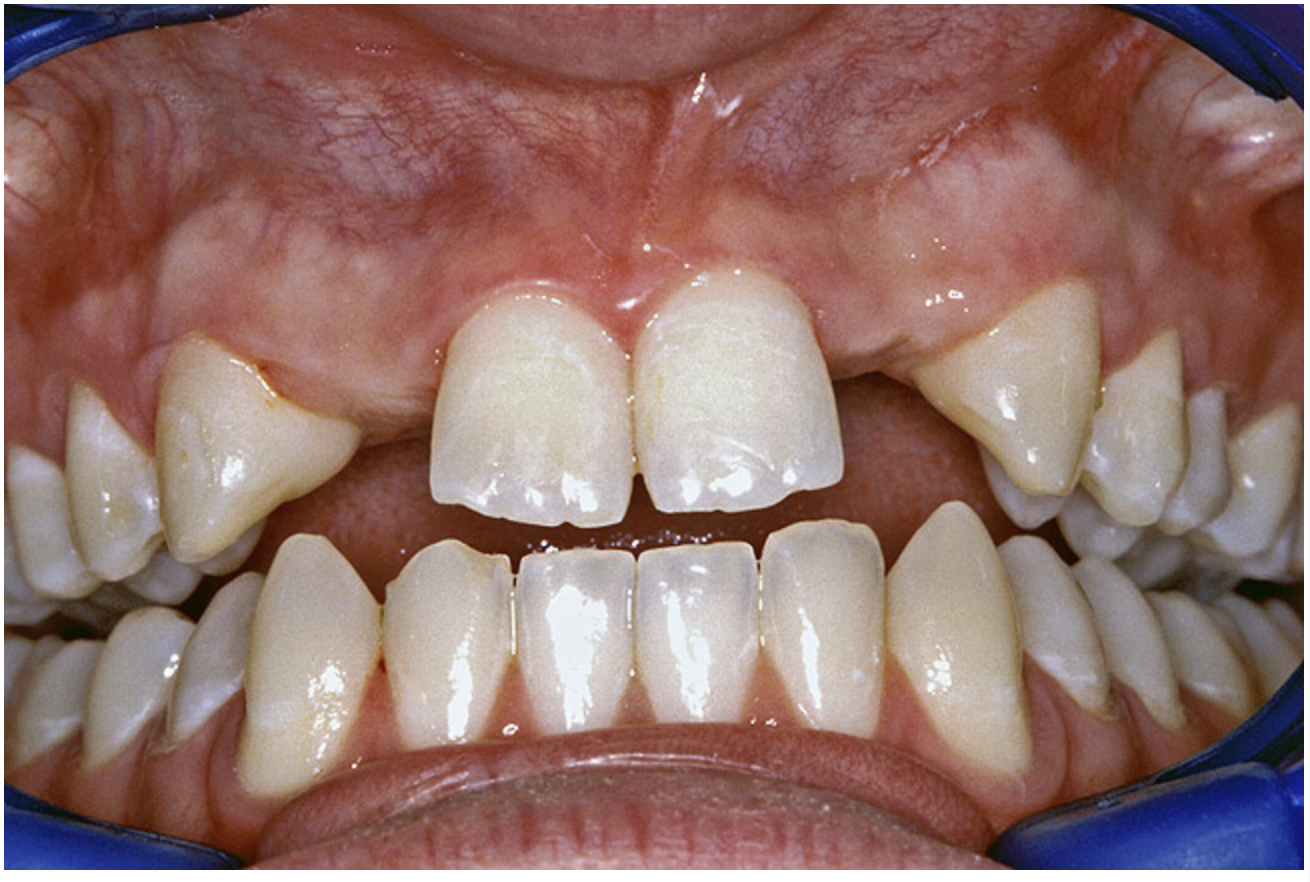

A 17-year-old boy presented with a history of congenitally missing maxillary lateral incisors. The patient had been under the care of an orthodontist for several years to manage his occlusion during his adolescent growth phase. The patient originally presented with his parents after being told that the “braces were ready to be removed, and their son was now ready for implants to replace the missing teeth.” This is not an uncommon circumstance, and unfortunately the orthodontic alignment was performed before the patient was sent to the restoring dentist. Therefore, the orthodontist was not aware of the space requirements for future implant placement. This case highlights the importance of proper communication between all members of the implant team, especially during the orthodontic planning phase. The patient’s medical history was unremarkable, and the patient was found to be healthy and a good potential candidate for dental implants to replace the missing lateral incisors.

Periapical radiographs were taken to help determine the mesial-distal inclinations of the adjacent tooth roots (Figure 1). The radiographs revealed a serious issue, convergent roots for the right canine and right central, which eliminated that area as a potential implant-receptor site. The space between the left central and canine teeth was minimal, although the roots were relatively parallel. Clinical examination (manual palpation of the root eminences superiorly to the vestibule on the right side) confirmed the root convergence (Figure 2A). The flat, wide zone of the keratinized tissue and lack of interdental papilla was evident for the missing right lateral incisor. There was a marked difference in clinical appearance for the left lateral, which could impact the eventual plan of treatment (Figure 2B). Other significant clinical findings included bilateral facial bone concavities, which existed as a result of the congenitally missing tooth roots. As a diagnostic cue to the underlying bone topography, it is important to follow the demarcation between attached and unattached gingival tissue, and note the crestal width of the available keratinized tissue (Figure 2C).

Figure 2a  Pretreatment buccal views showed (A) root convergence, (B) a difference in clinical appearance of the left lateral, and (C) significant crestal width of keratinized tissue.

Figure 2b  Pretreatment buccal views showed (A) root convergence, (B) a difference in clinical appearance of the left lateral, and (C) significant crestal width of keratinized tissue.

Figure 2c  Pretreatment buccal views showed (A) root convergence, (B) a difference in clinical appearance of the left lateral, and (C) significant crestal width of keratinized tissue.